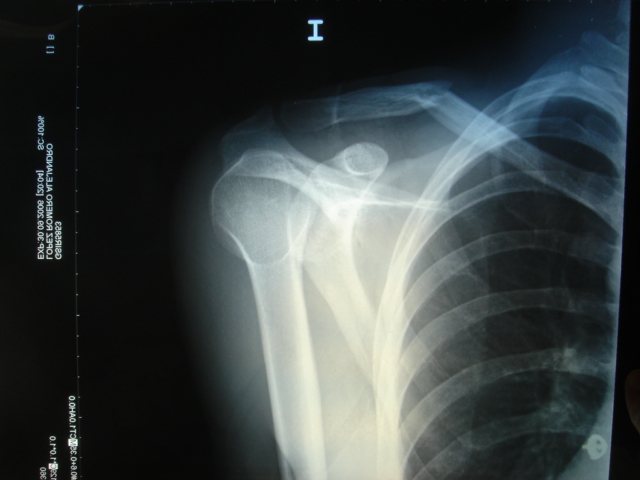

Nos visita en nuestra consulta de Sevilla este torero que en un lance en un festejo reciente atendido por otro equipo médico sufre un percance que le afecta una de sus clavículas.

Dué trasladado al Hospital de Rio Tinto donde le aplicaron un vendaje para inmolvilizar y retrotraer el hombro afecto,

Lo estudiamos y revisamos el hombro, la inmovilización, las Rx etc.

En las imágenes que se adjuntan se aprecia como en estos casos de fractura o luxacion de hombro, clavícula o brazo en general; el miembro sano sujeta el afectado. Siendo lo que se pretende, impedir movimiento doloroso de la parte que molesta.

En el estudio radiológico se aprecia claramente la fractura y su grado de desviación del eje normal que es de ángulo pequeño, lo que evita otro procedimiento quirúrgico cruento.